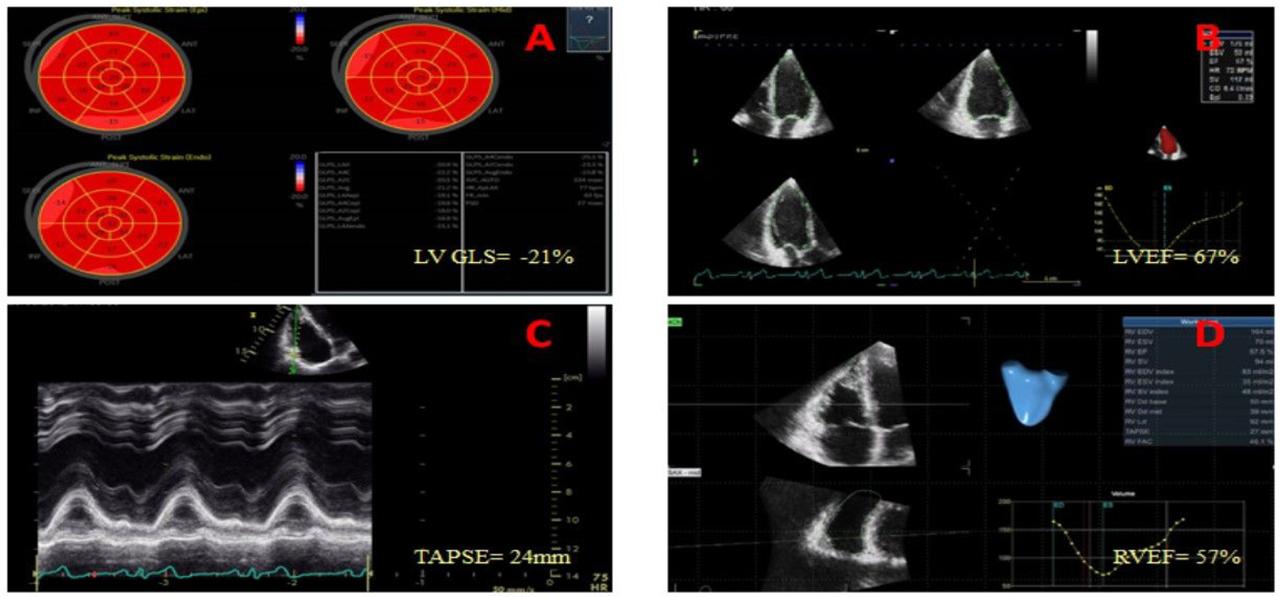

Baseline echocardiographic evaluation of left ventricular and right ventricular function. Panel A. Normal range left ventricular 2D global longitudinal strain value; Panel B. 3D echocardiographic quantification of left ventricular volumes and ejection fraction showed values within normal limits; Panel C. M-mode analysis with normal tricuspid annulus systolic excursion; Panel D. 3D echocardiographic assessment of the right ventricle revealed also normal volumes and function.